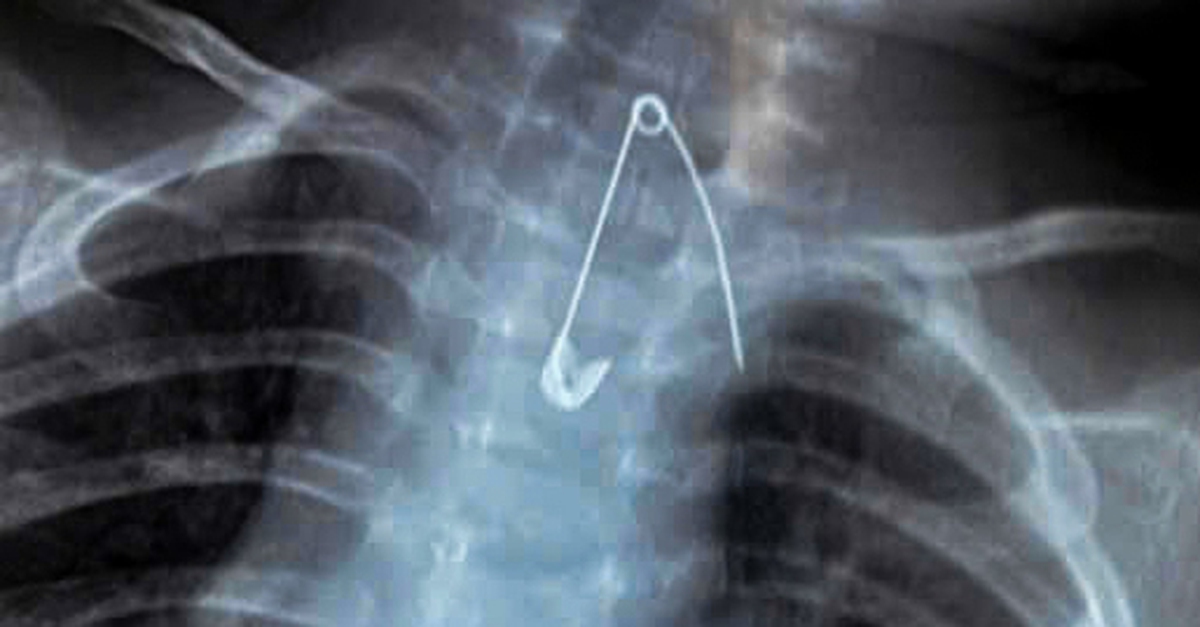

Cứu sống hai em bé nuốt kim băng và cây kẹo mút

Ngày 8-1, Bệnh viện Sản Nhi Cà Mau cho biết các bác sĩ vừa tiếp nhận và xử trí thành công hai trường hợp bệnh nhi nuốt dị vật đặc biệt nguy hiểm, trong đó có ca thủng tá tràng và ca dị vật sắc nhọn nằm sát động mạch chủ, đe dọa đến tính mạng.